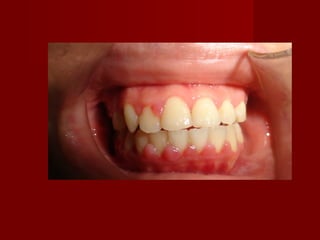

 ( c ) Hawley retainer( c ) Hawley retainer with auxillary springswith auxillary springs

for correction of anterior crossbitefor correction of anterior crossbite

 If space is availableIf space is available

– procline the lingually erupted anterior teethprocline the lingually erupted anterior teeth

with RA or FAwith RA or FA

– RA by using z springRA by using z spring

 modified finger springmodified finger spring

 palatal springpalatal spring

 Cranked palatal springCranked palatal spring

 cross cantileaver springcross cantileaver spring

 screwscrew

 If the (reverse) OB is more than 2mm or theIf the (reverse) OB is more than 2mm or the

opposing teeth are periodontally compromised,opposing teeth are periodontally compromised,

the use of a posterior bite plane.the use of a posterior bite plane.

-To allow the tooth to be moved free from occlusion.-To allow the tooth to be moved free from occlusion.

– To decrease or eliminate the forces exerted on theTo decrease or eliminate the forces exerted on the

teeth in the opposing arch.teeth in the opposing arch.